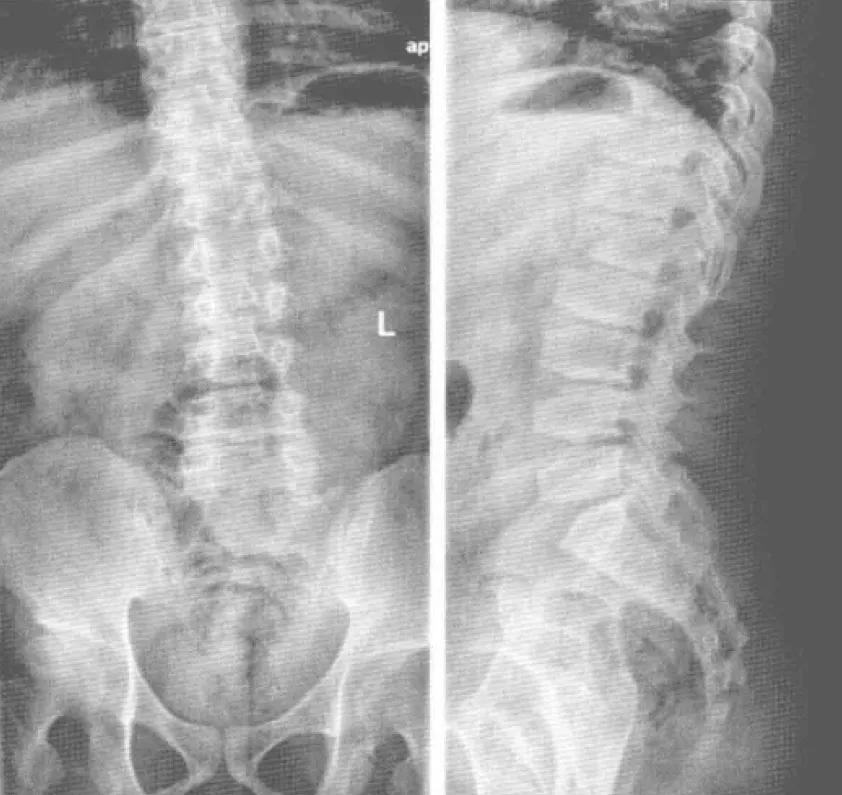

晚发型脊椎骨骺发育不良( spondyloepiphysealdysplasia tarda, SEDt)是一类累及脊椎椎体和骨骺的骨软骨发育不良性疾病,具有高度的遗传异质性。晚发型脊椎骨骺发育不良是由SEDL基因突变引起的罕见的X连锁隐性(XR)遗传病。临床上,主要表现为短躯干性侏儒,但智力正常,无头面部畸形。本病发病较晚,故称为晚发型脊椎骨骺发育不良。目前认为本病病因和发病机制可能为原胶原蛋白II 基因突变所致,该致病基因位于X染色体的短臂末端。X连锁晚发型脊椎骨骺发育不良通常是男性发病(图3-5-1、图3-5-2),女性只携带致病基因而表型正常。致病后软骨成骨受到影响,从而导致脊椎骨骺及长骨骨骺的不发育或发育落后,形成了短躯干侏儒的典型身材、脊椎骨的驼峰状改变。 本病均有不同程度腰背及髋、膝疼痛和活动受限。共同体征:颈短肩高,桶状胸,步态蹒跚,智力正常的短躯干型侏儒;血液生化检查均正常。身材矮小是本病临床特征之一,一方面由于软骨发育障碍,椎体变扁,椎间隙及关节间隙均变狭窄,造成患者身材矮小;另一方面,由于软骨发育障碍,软骨下骨化异常,造成骨发育受限。虽然本病的确切机制不详,但骨发育异常是本病患者身材矮小的另个 主要原因。影像表现1、 X线平片及CT表现脊椎表现,由于软骨发育不良的主要病理改变为软骨的过度增生和成熟障碍,造成关节软骨持续性退化、丢失和骨破坏,骨密度下降,其结果是长骨的骨端进行性膨大及骨质增生,关节间隙逐渐狭窄;椎体变扁,二次骨化中心形成障碍,从而影像上早期出现明显骨关节退行性改变,使椎体呈横置花瓶状和*弹子**头状改变,胸椎中段及腰椎明显,椎间隙明显变窄,脊柱侧弯。由于椎体软骨发育异常,椎间盘与椎体的连接不稳定,椎间盘容易发生疲劳损伤导致椎间盘变性,椎问隙变狭窄,椎体表面终板凹凸不平,并可出现多个凹陷切迹,为史莫结节改变,椎间隙内可出现低密度影( 真空征),双侧肋骨表现后肋窄小,前段宽呈飘带状,但椎弓根显示正常。

X线片上①骨盆改变主要表现为骨盆狭小,髂骨和骶骨发育小,骶骨耳部发育不良,坐耻骨支相对增大呈直立状,坐骨大切迹上缘呈直角状,闭孔增大;②髋关节改变,表现为髋臼外上缘发育不良,变浅,髋白角加大,关节面不规整及硬化;③股骨头发育小且扁,关节面欠光滑,股骨颈粗短,颈干角小,髋内翻; ④四肢大关节主要表现为关节发育不良 导致较早地发生退行性改变。膝关节改变,股骨两髁平坦,髁间窝变浅,胫骨髁间隆突变平甚至消失,膝关节关节面失去其自然弧度,关节间隙变窄。